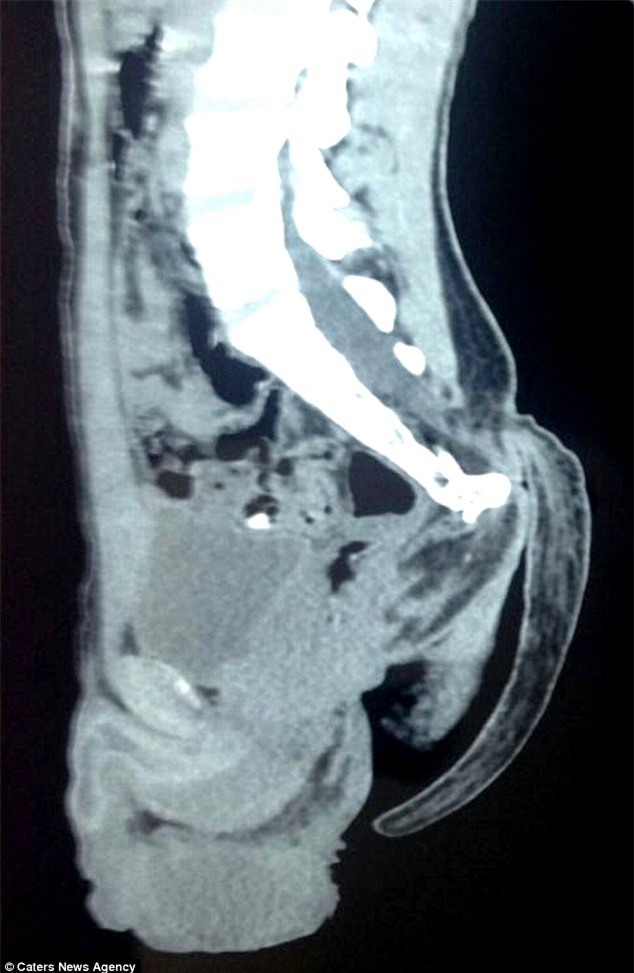

Hình ảnh chụp phim x-quang của bệnh nhân thể hiện rõ chiếc đuôi dài |